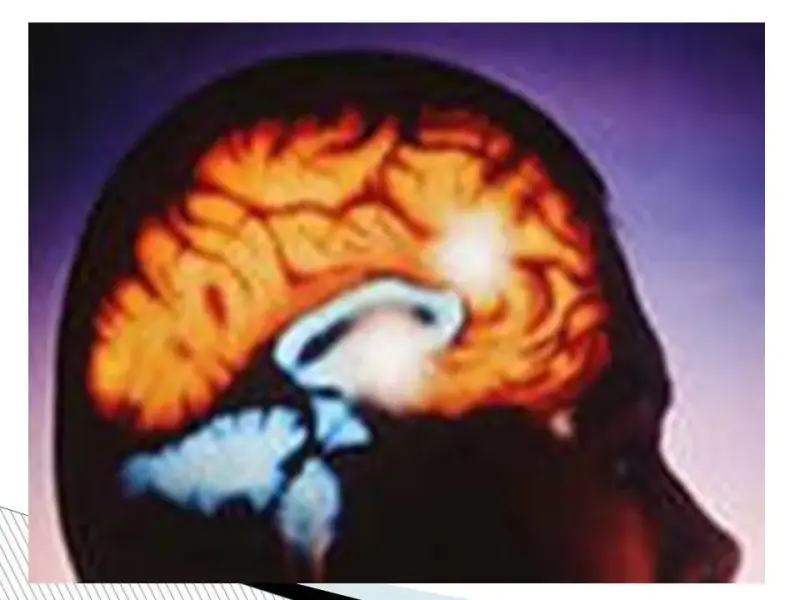

Выработка половых гормонов. В период полового созревания гипофиз, находящийся в основании головного мозга, начинает усиленно вырабатывать вещества, называемые гормонами. Они стимулируют выработку половых гормонов, регулирующих изменения, которые с вами происходят, в том числе влияют на менструацию, и регулирует менструальный цикл. Женские половые гомоны – эстрогены.

Органом регулятором яичников является гипофиз, который находится в головном мозге и синтезирует фолликулостимулирующий (ФСГ) и лютеинизирующий гормоны (ЛГ). В свою очередь, главным органом-мишенью для гормонов яичников, является матка. Другие органы мишени: молочные железы, влагалище, мочевой пузырь, кожа, волосяные фолликулы, кости, сосуды и многие другие. Поэтому недостаток половых гормонов проявляется очень многообразно.

Фолликулярная фаза. Фолликулярная фаза начинается с первого дня новой менструации и продолжается половину менструального цикла до овуляции (выхода новой яйцеклетки). Под действием гормонов гипоталамуса и гипофиза (отделы головного мозга) в одном из яичников начинают расти фолликулы с яйцеклетками, из которых созревает только один (реже два). Эта часть цикла называется фолликулярной фазой и занимает примерно первую половину менструального цикла, однако у разных женщин продолжительность ее может быть различной. Имеется целый ряд причин, влияющих на срок наступления овуляции: стрессы; путешествия; переезды; болезнь; индивидуальные особенности организма